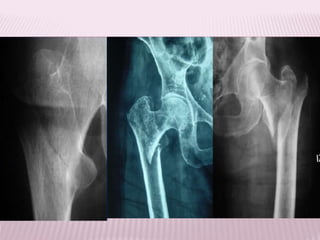

FRACTURA TRANSTROCANTÉREA

 Se refriere a la solución de continuidad en la

zona metafisiria proximal de fémur

comprendida entre los 2 trocánteres.

FRACTURA INTERTROCANTERICA

FRACTURA SUBTROCANTÉREA